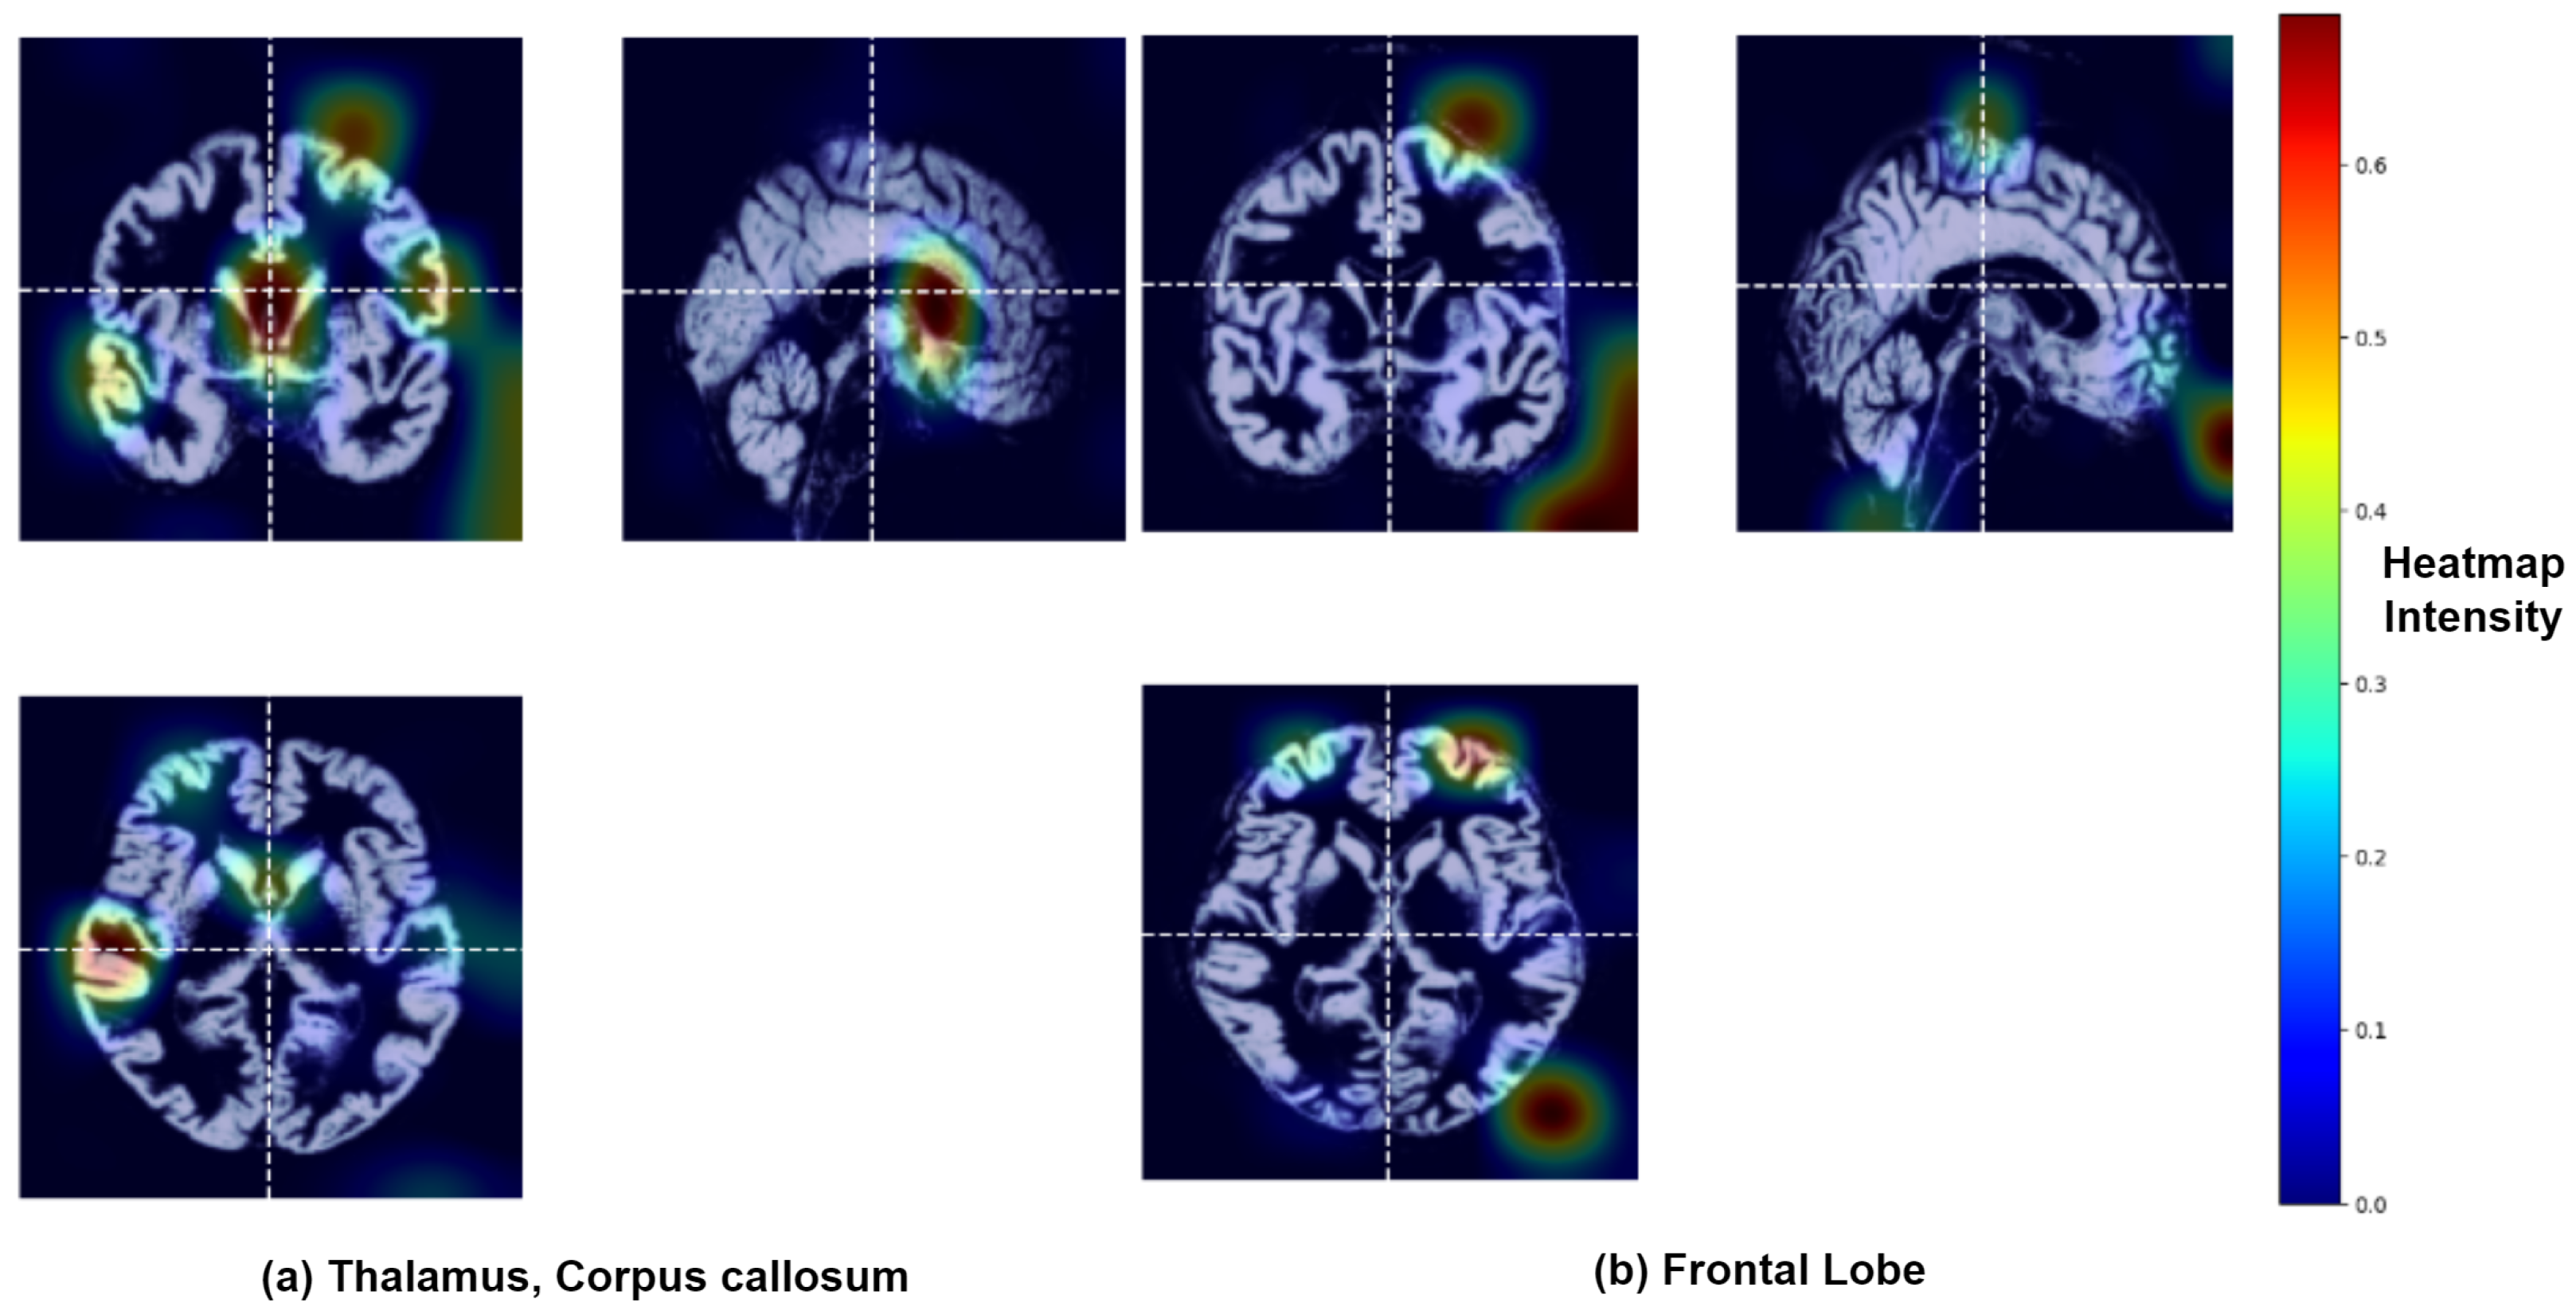

3.2. Identification of Brain Regions Affected by Major Depressive Disorder

| SI No. | Brain Regions | Functionalities |

|---|---|---|

| 1. | Frontal Lobe | Planning, decision-making, problem-solving, voluntary motor control, behavior, emotional regulation, speech and hearing |

| 2. | Parietal Lobe | Integration of somatosensory information like touch, pain, temperature, proprioception, spatial orientation, perception, aspects of language and mathematical processing |

| 3. | Temporal Lobe | Primary auditory processing, language comprehension, encoding and retrieval of declarative memory, visual object and face recognition and emotional processing |

| 4. | Thalamus | Regulation of consciousness, memory, emotion, alertness, sleep-wake cycles, relaying sensory and motor signals to the cerebral cortex |

| 5. | Insular Cortex | Involved in interceptive awareness, taste processing, automatic control, pain perception and emotional regulation |

| 6. | Corpus Callosum | Communication and coordination of motor, sensory and cognitive functions |